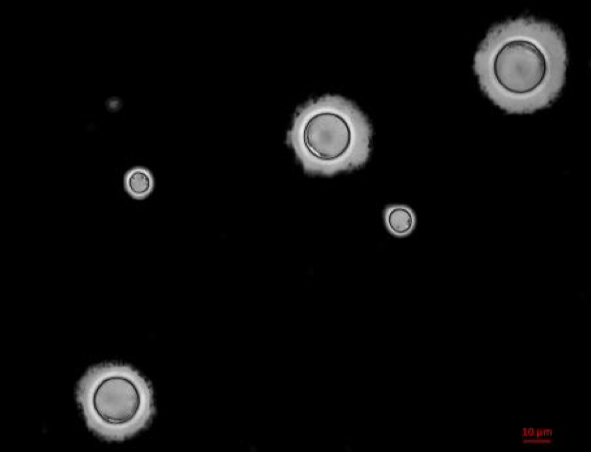

Cryptococcus neoformans